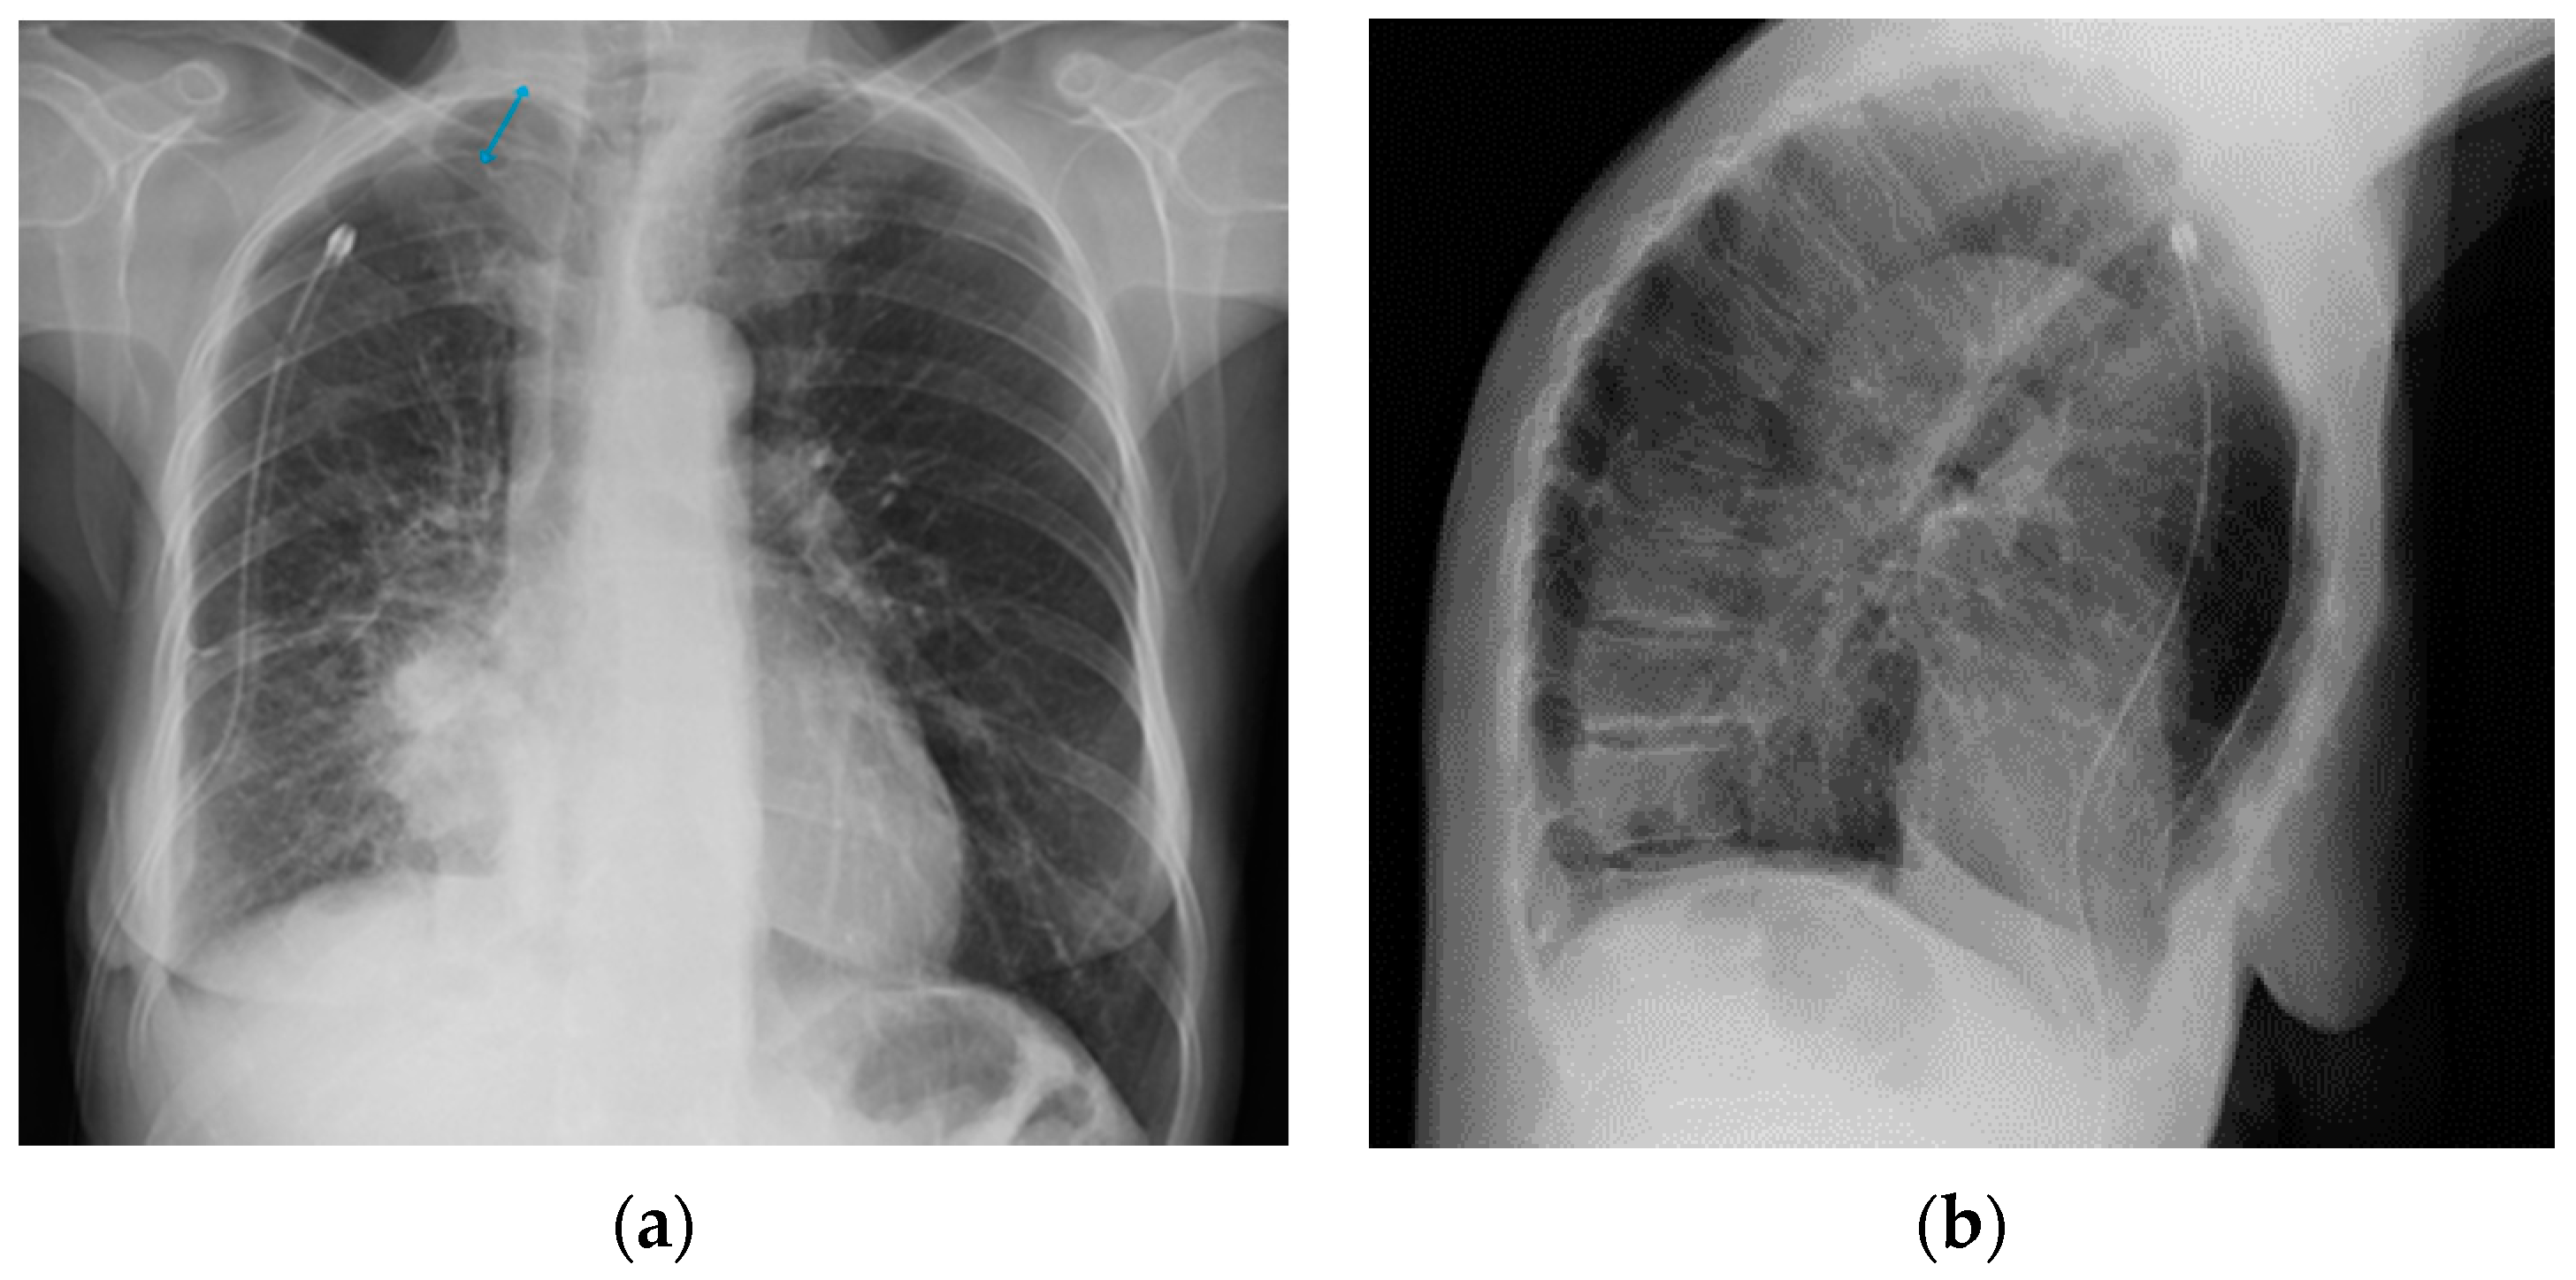

9. Deep-Learning-Based Algorithms for Chest Devices’ Detection on CXR: A Glimpse into the Future

- Irmici, G.; Cè, M.; Caloro, E.; Khenkina, N.; Della Pepa, G.; Ascenti, V.; Martinenghi, C.; Papa, S.; Oliva, G.; Cellina, M. Chest X-ray in Emergency Radiology: What Artificial Intelligence Applications Are Available? Diagnostics 2023, 13, 216. [Google Scholar] [CrossRef]

- Yi, X.; Adams, S.J.; Henderson, R.D.E.; Babyn, P. Computer-aided Assessment of Catheters and Tubes on Radiographs: How Good Is Artificial Intelligence for Assessment? Radiol. Artif. Intell. 2020, 2, e190082. [Google Scholar] [CrossRef] [PubMed]